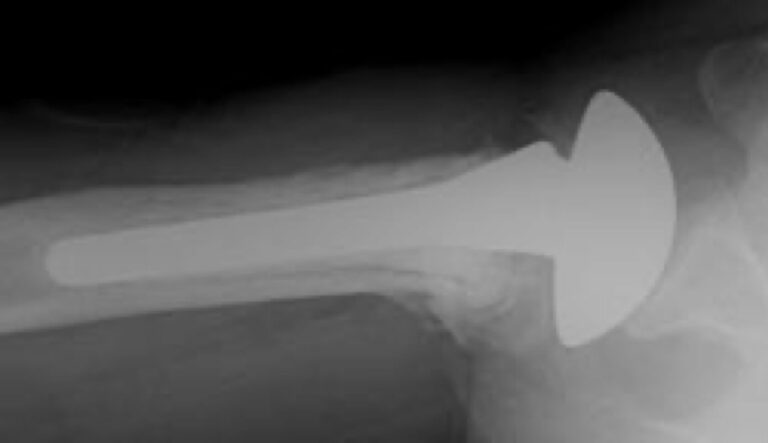

DePuy, Global Fracture